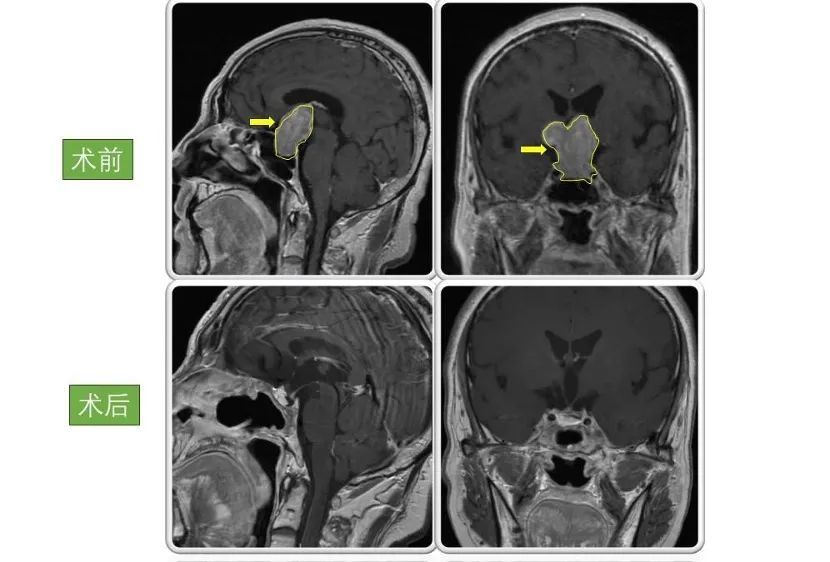

男性,46岁 因“突发头痛伴恶心呕吐、双眼视物不清12小时”入院。入院检查显示巨大垂体腺瘤,大小为4.5×4×4cm。

术后患者双眼视力明显好转,病情稳定后出院,现恢复良好,定期复查。